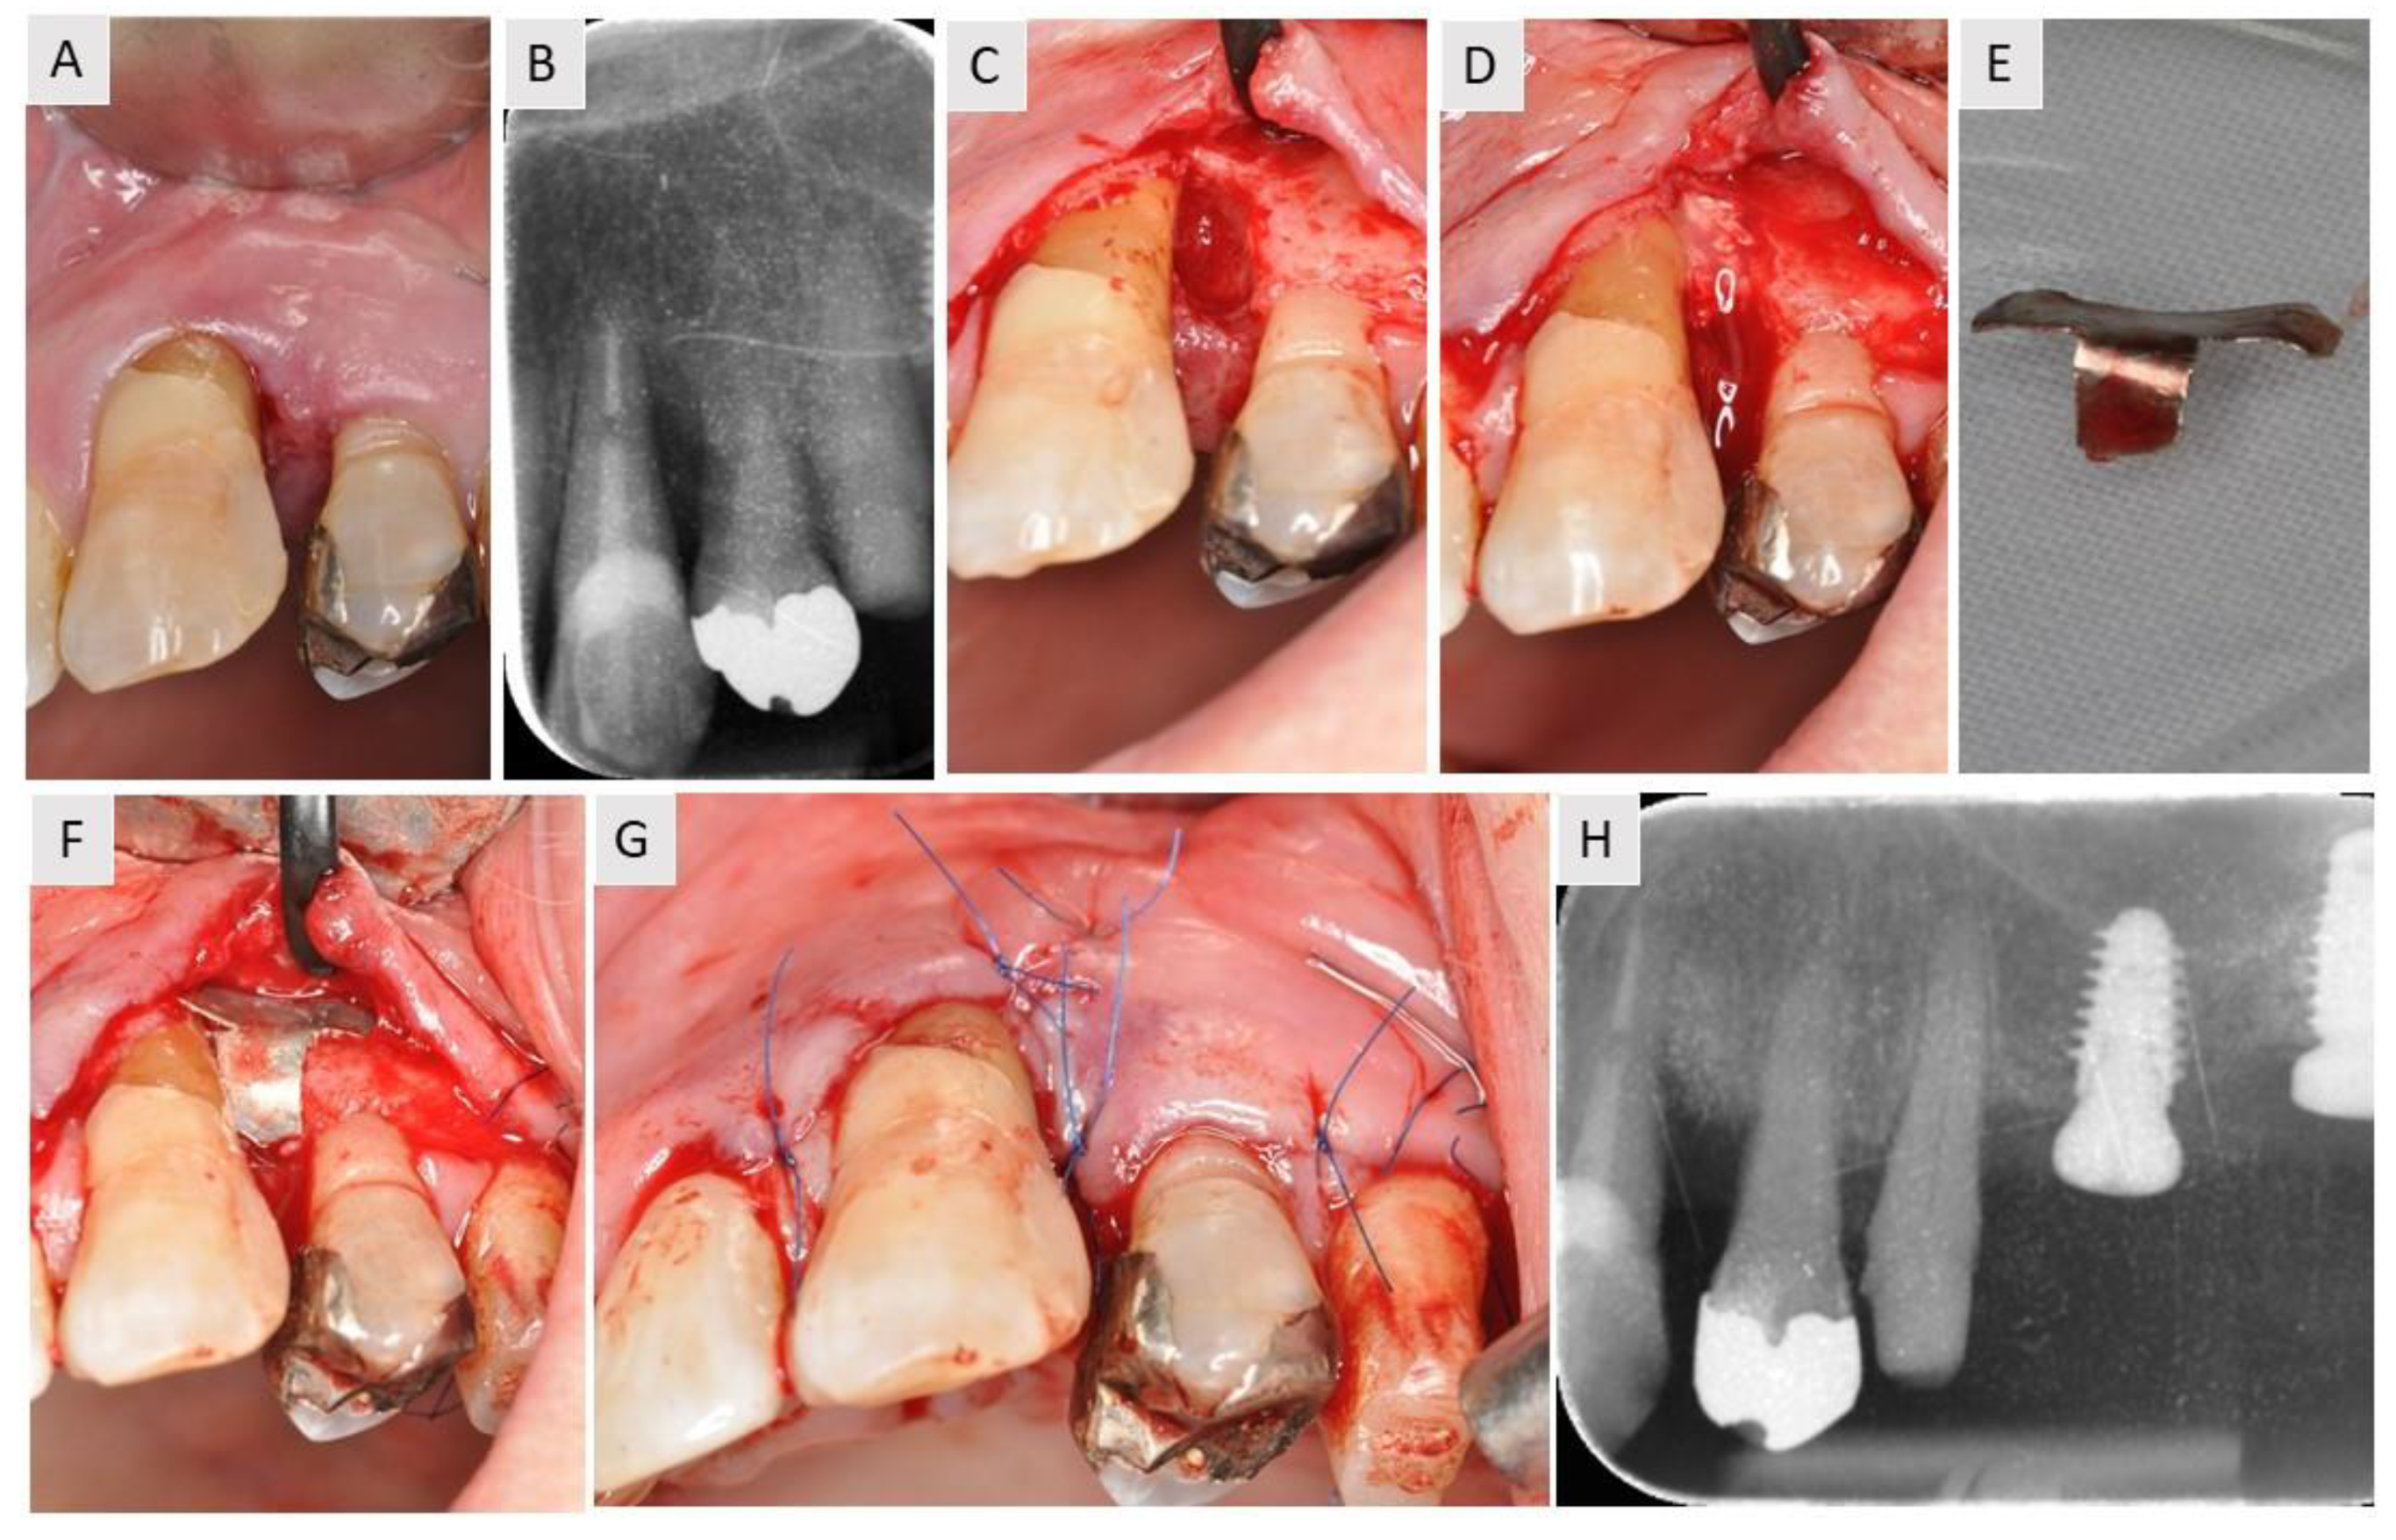

3.1. Case 1